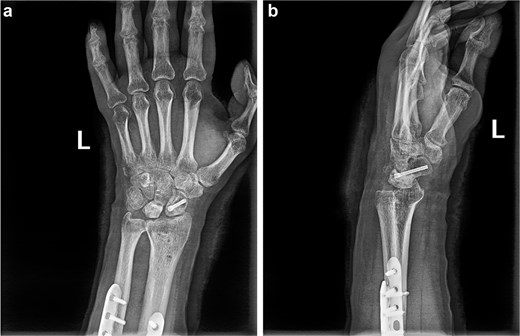

(a and b) Anterior and lateral views of the wrist joint following the second postoperative intervention, demonstrated satisfactory reduction of the fracture ends of the wrist bones, and the lunate bone had been relocated.

(a and b) Anterior and lateral views of the wrist joint after 6-month follow-up.